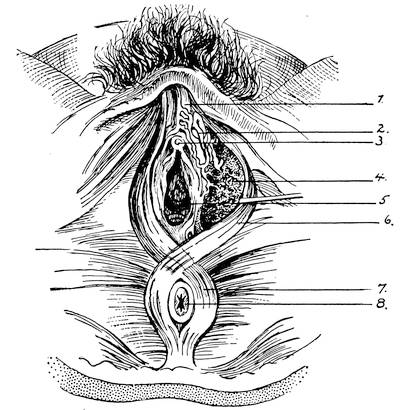

Mons of Venus, labia majora, minora, vestibule, bulbs, clitoris, Bartholinian glands, hymen, vagina, uterus, broad and round ligaments, viiitubes, ovaries, Graafian follicle, ovum.

F. The Female External Genitals

In the female the vestibule, or the shallow depression which was formed through the breaking through of the urogenital membrane, remains open throughout life, and is termed the vestibule of the vulva. From the sides of the lower part of the sinus a pair of evaginations are formed and give rise to the Bartholinian glands. The vestibule being in fact the open sinus urogenitalis, the urethra and the vagina naturally have their orifices in the same.

The genital tubercle ceases to grow in the female and becomes the clitoris. The genital folds or the lips of the vestibule become prolonged and form the labia minora or the nymphae. The genital swelling increases in size through adipose and fibrous tissue. The part situated on the ventral side of the clitoris becomes the mons veneris, while the lateral parts are converted into the labia majora of the vulva.